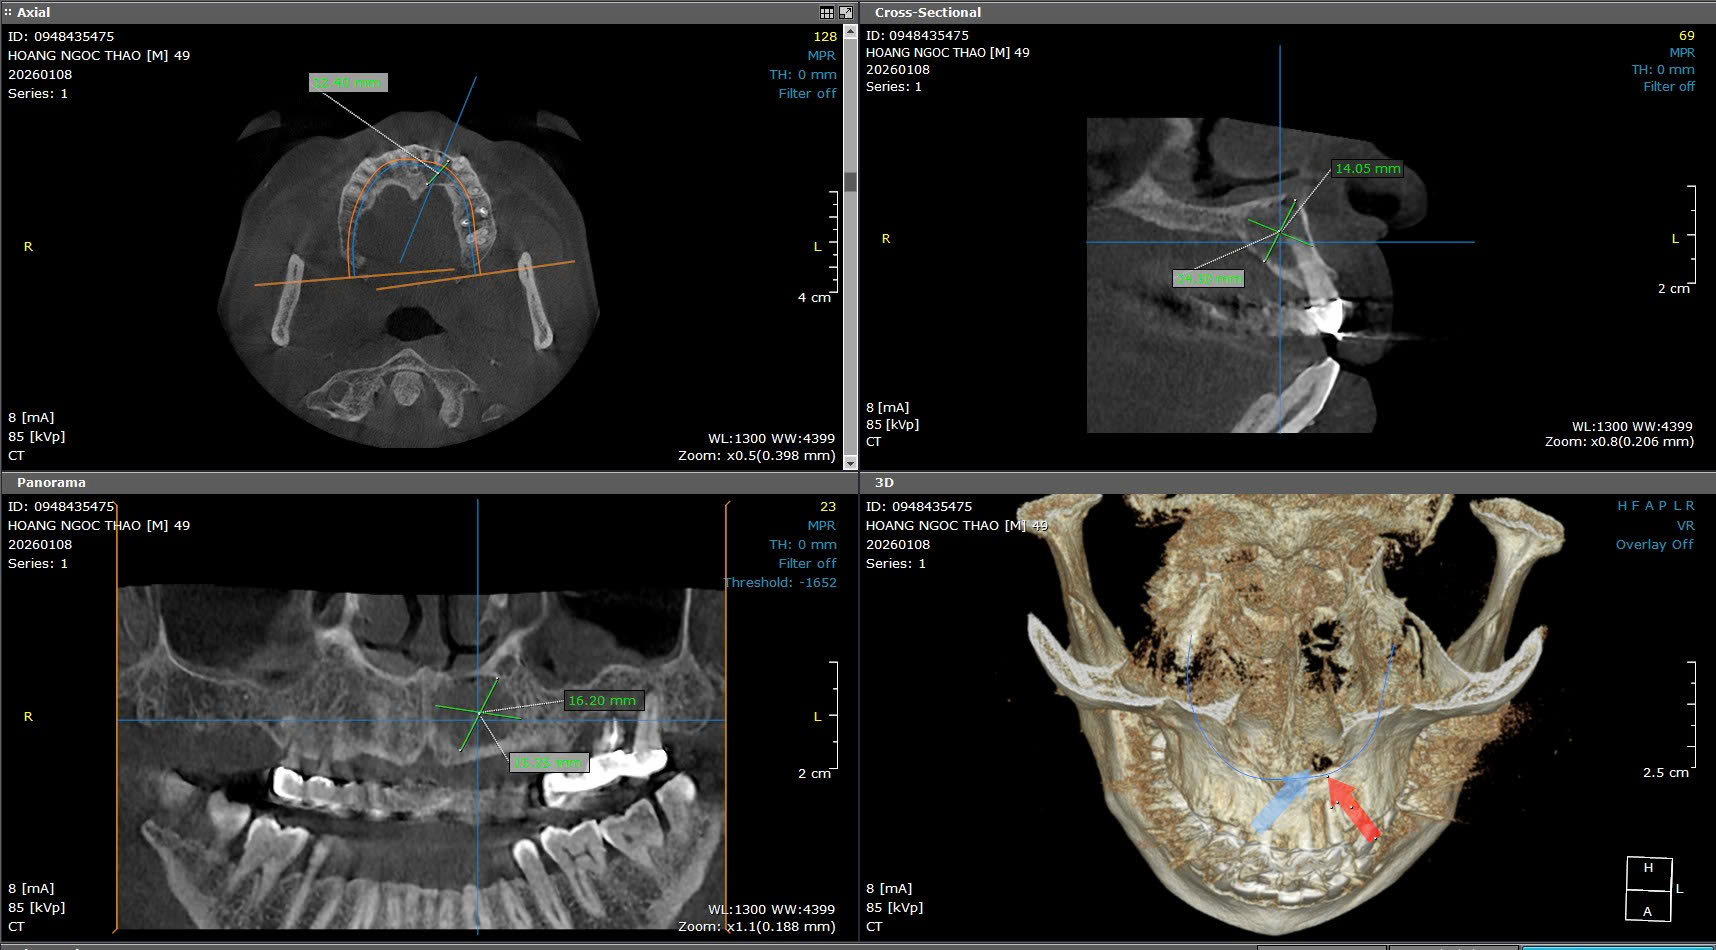

Mở thông nang giảm áp sử dụng lỗ thông kết hợp máng kỹ thuật số

Mở thông nang điều trị nang chân răng hàm dưới